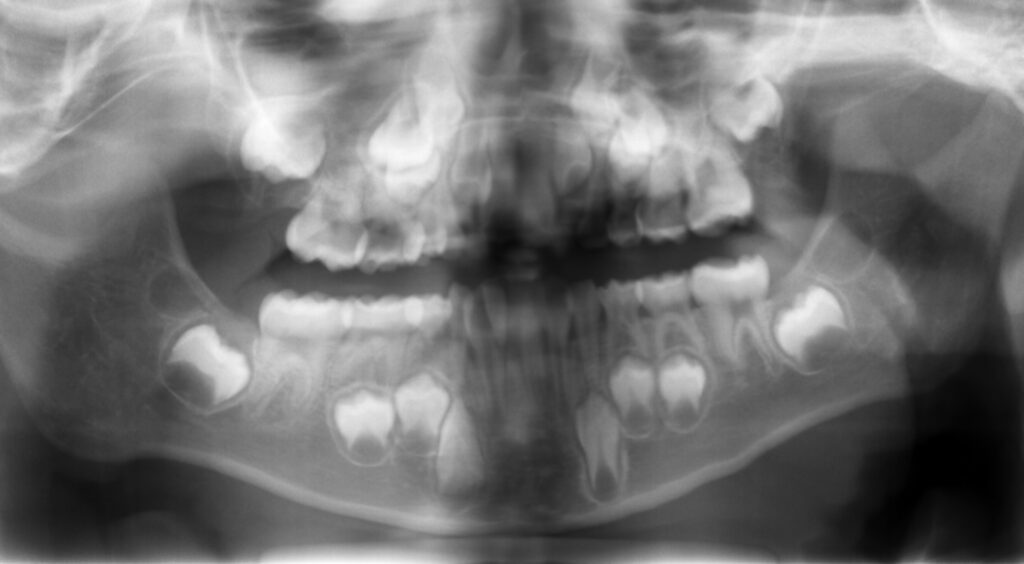

▶︎レントゲンを撮ることで、

歯や顎の大きさや虫歯の可能性を伝えることができます。